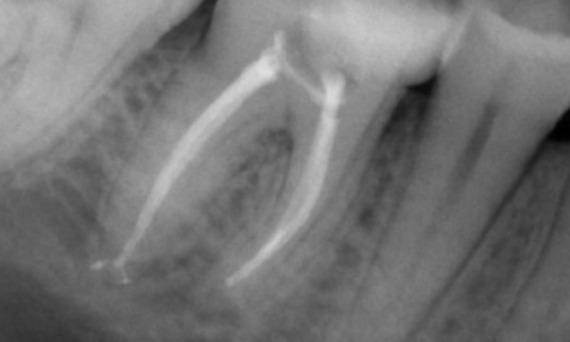

"I chose TruNatomy to be able to preserve as much dentin as possible to overcome occlusal load and increase the longevity of the tooth." - Dr. Abuelezz

Before: Upon examination, there was a caries lesion related to the lower right first molar. Radiographic examination revealed proximity of the lesion to the pulp horn and combining it with the chief complaint, a final diagnosis of chronic irreversible pulpitis was concluded.

After: Access cavity was done as conservative as possible. TruNatomy was the system of choice due to the young patient’s age. We needed to preserve dentine as much as possible to increase the tooth ability to overcome occlusal load and increase the longevity of the final restoration.

Cairo, Egypt